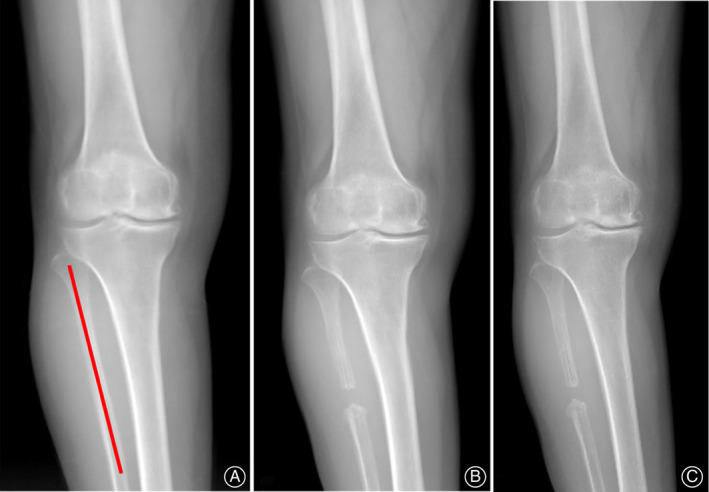

Figure 1 illustrated the methods of measurements in the above‐mentioned radiographic parameters. All radiological parameters were obtained with the assistance of picture archiving and communication systems (PACS; Science & Technology General Company of Hebei Medical University, Shijiazhuang, China). The radiographs were evaluated by two observers (H.Z.H and Z.Z.W), independently of each other, to measure the K‐L classification, HKA, FTA, and settlement value. One observer repeated the measurements after 2 weeks.

Fig. 1.

(A)The hip‐knee‐angle angle (HKA) of the lower extremity is the angle calculated by intersecting the line between femoral mechanical and tibial mechanical axes; (B) The femorotibial angle (FTA) was defined as the lateral angle between the femoral anatomical axis and the tibial anatomical axis; (C) The settlement value of medial tibial platform (dashed line) was defined as a perpendicular distance from the medial edge of platform to a tangential line (yellow line) which is perpendicular to the mechanical axes of the tibial (red line).